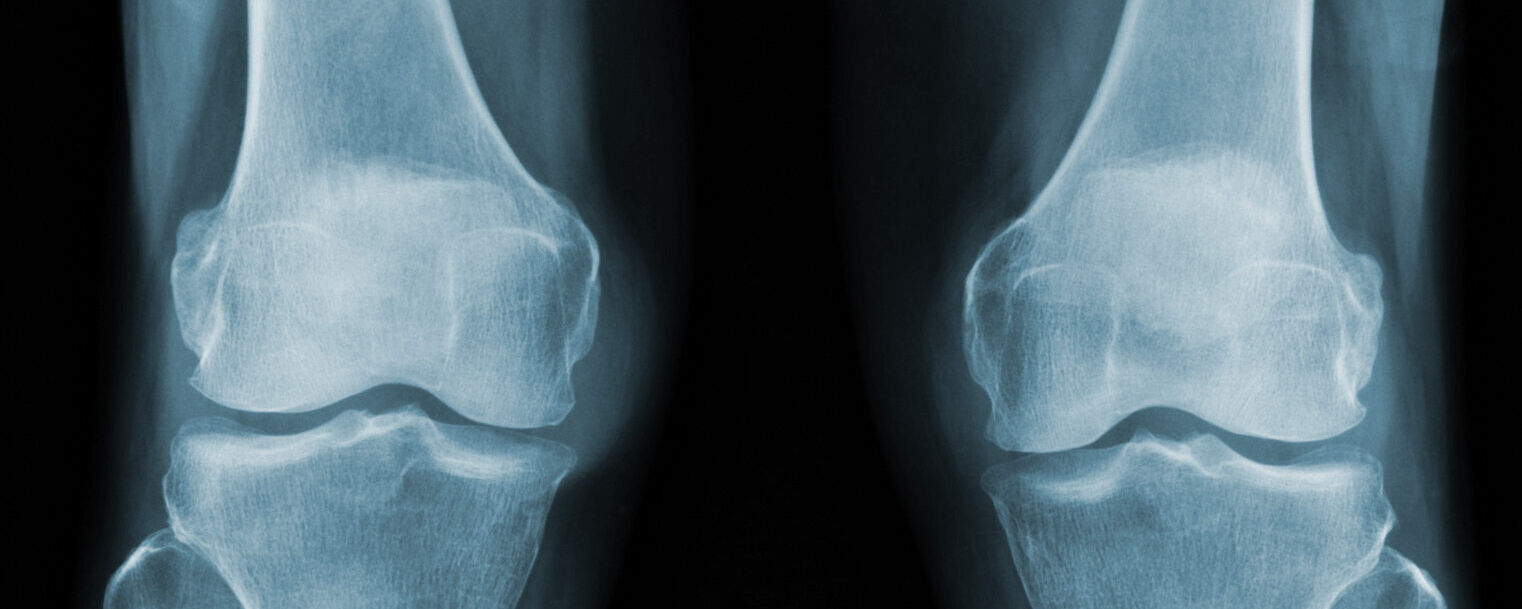

Tibial Plateau Fracture

A tibial plateau fracture is a break at the top of the shin bone (tibia), it forms part of the knee joint. This area is important for weight-bearing and knee stability, so injuries here can be serious and need careful management.

Diagnosis

Your doctor will examine your knee and order X-rays to identify the fracture. A CT scan is often used to assess the shape and severity of the break in more detail. An MRI may be needed to check for associated ligament or meniscus injuries, which are common with this type of fracture.